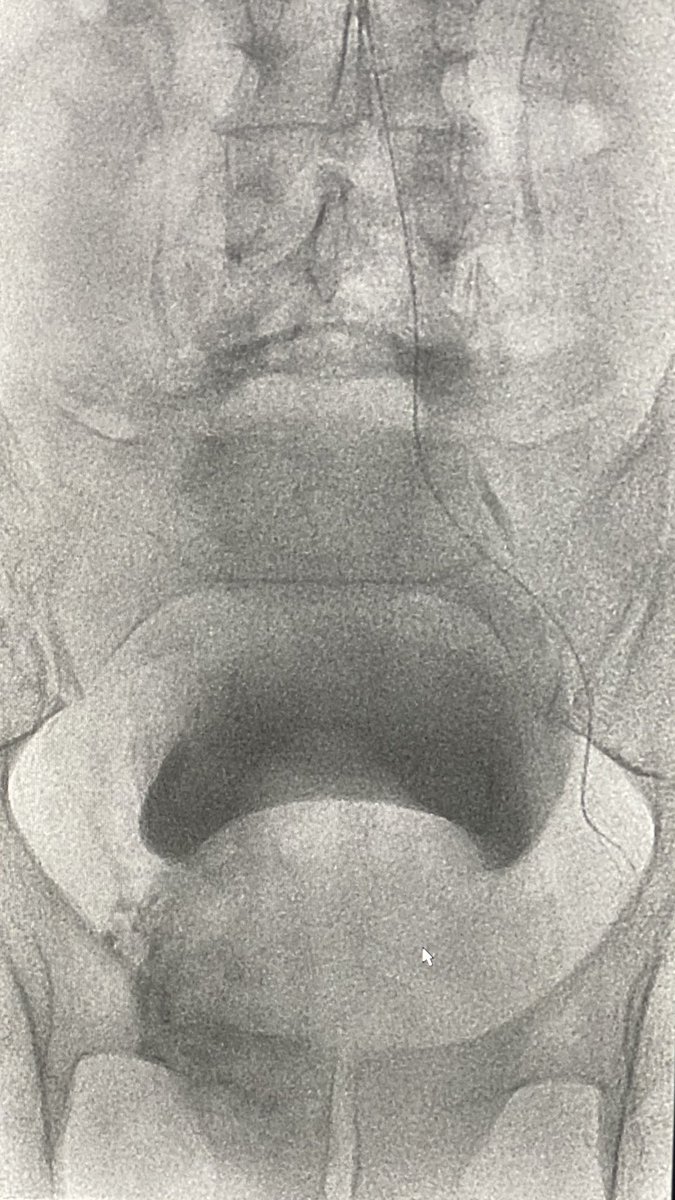

61yr with a whopping 306 cc prostate. #radialfirst #PAE. 1720 mGy. Discharged 90 min post #irad procedure. What’s the biggest prostate would you consider for PAE? @BSIR_News @pairsmedia @cirsesociety @AriIsaacsonMD @TiagoBilhim @BryantTimo